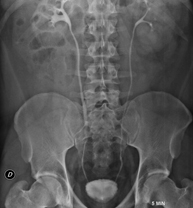

- RX Abdomen

Técnica mediante la cual, utilizando rayos X, se obtienen imágenes del abdomen (estómago, intestino delgado, intestino grueso, hígado, riñones, vejiga, pelvis ósea, etc.) para su estudio.

Una radiografía de abdomen es una técnica mediante la cual, utilizando una pequeña dosis de radiación, se obtiene una imagen bidimensional del abdomen con sus estructuras anatómicas (estómago, intestino delgado, intestino grueso, hígado, páncreas, riñones, vejiga, pelvis ósea, etc.).